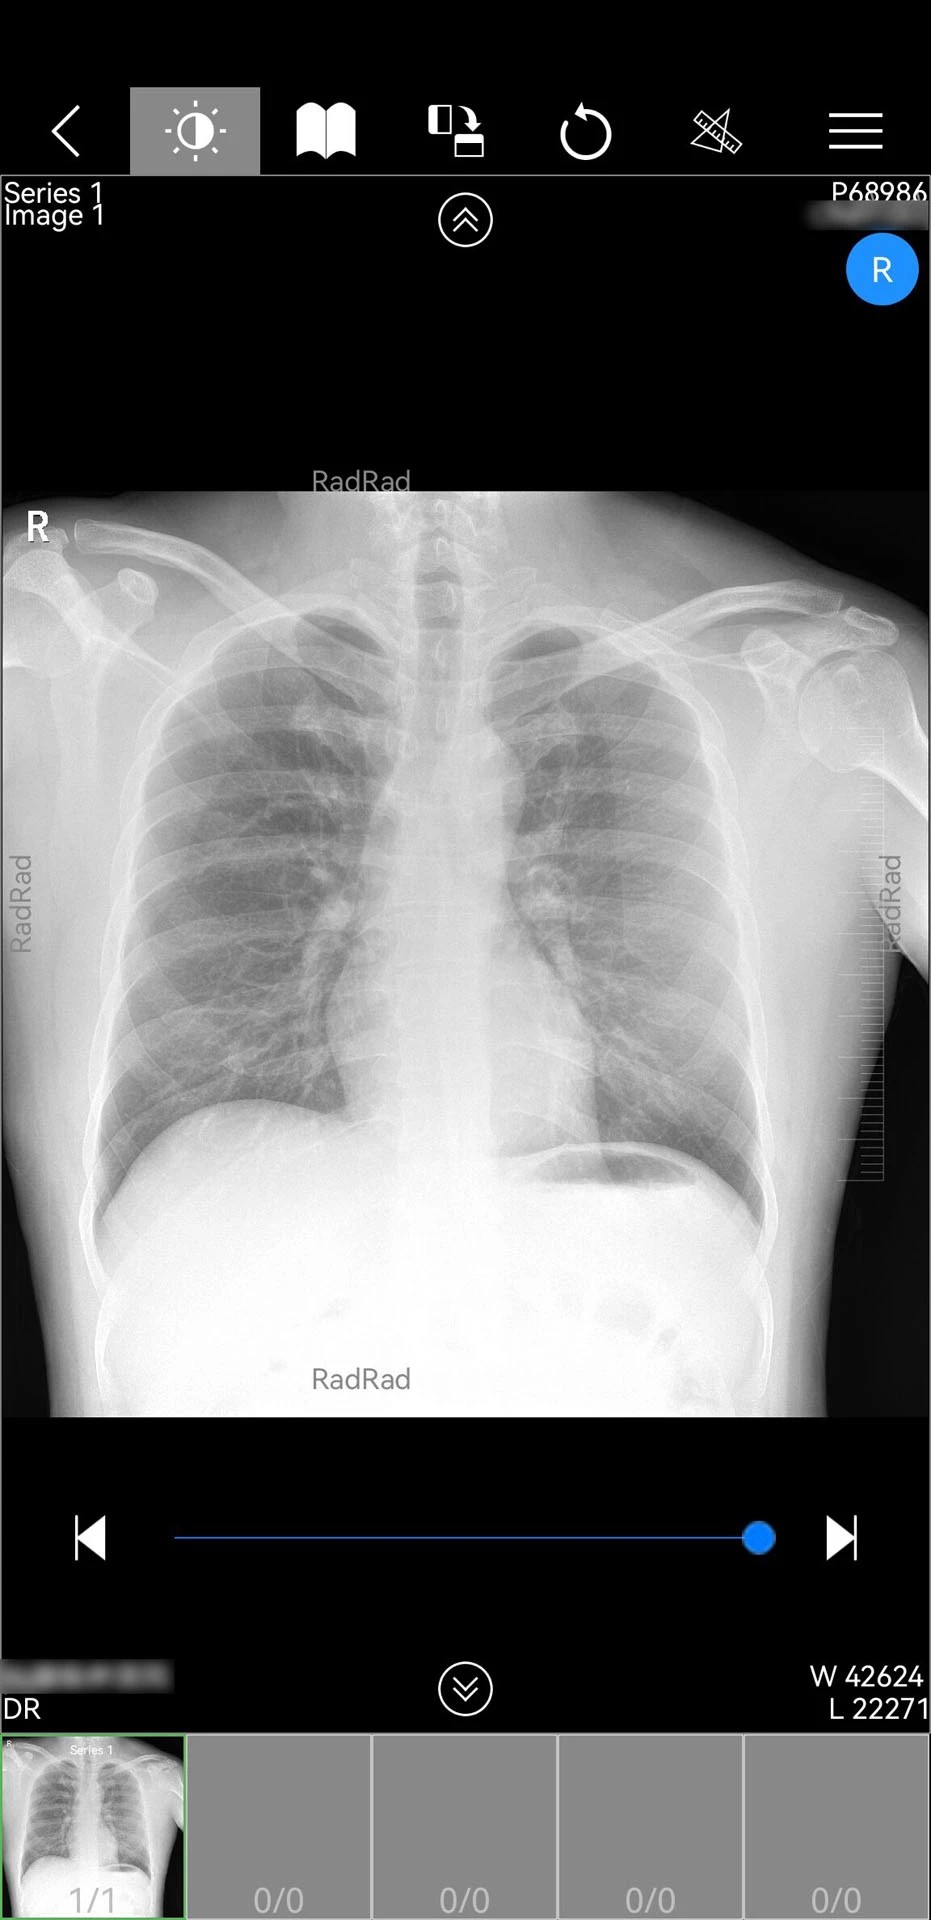

1. 核心功能模块:包含患者管理、影像调阅、在线问诊、医生协作四大基础功能。患者管理支持分组标记与诊后随访,影像调阅可实时查看CT、MRI等检查的原始影像及报告,在线问诊提供图文、语音、视频三种沟通方式,医生协作支持跨院会诊与病例共享。

2. 影像处理能力:定制版新增CT三维重建服务,可将二维切片数据转化为三维立体模型,支持任意角度旋转、缩放及透明度调节,帮助医生更直观地观察病变位置与周围组织关系。同时集成多模态影像融合技术,可同步显示CT、PET、MRI等不同影像的叠加效果。

3. AI辅助诊断:内置深度学习算法,可自动识别肺结节、骨折、脑出血等20余种常见病变,标注病变位置并生成结构化报告。AI分析结果与医生诊断意见可并排显示,供医生参考对比,提升诊断效率与准确性。

1. 专业影像处理:作为国内少数具备完整影像处理能力的医疗APP,定制版支持从影像调阅、三维重建到AI分析的全流程操作,满足影像科医生的专业需求。